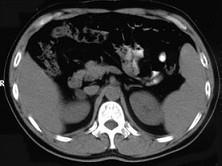

问题 女,23岁,满月脸、向心性肥胖,CT扫描如图所示,应诊断为 ( )

选项 A、右侧肾上腺嗜铬细胞瘤 B、右侧肾上腺转移瘤 C、右侧肾上腺腺瘤 D、右侧肾上腺腺癌 E、右侧肾上腺增生

答案 C